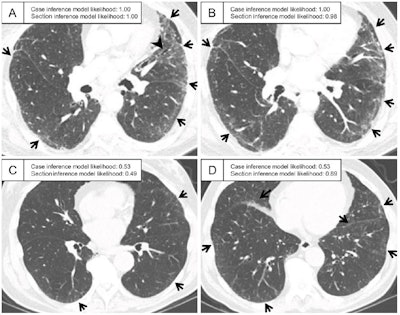

Representative CT scans assessed as having interstitial lung abnormality according to ground-truth labeling in the test set. (A, B) Axial CT images in a patient assigned a probability of 1.00 by the case inference model. The sections show ground-glass abnormality in the subpleural area of the bilateral lungs (arrows) and traction bronchiectasis in the lingula of the left lung (arrowhead in A). (C, D) Axial CT images in a patient assigned a probability of 0.53 by the case inference model. (C) Slight ground-glass abnormality is seen in the subpleural area of the bilateral lungs (arrows), and the probability assigned by the section inference model is moderate (0.49). (D) At the lower section level, ground-glass abnormality is more widespread (arrows), and the probability assigned by the section inference model is higher (0.89). The probabilities were calculated with the model using the three-label method in the section inference model and the two-label method and random forest classifier in the case inference model. Images and caption courtesy of the RSNA.